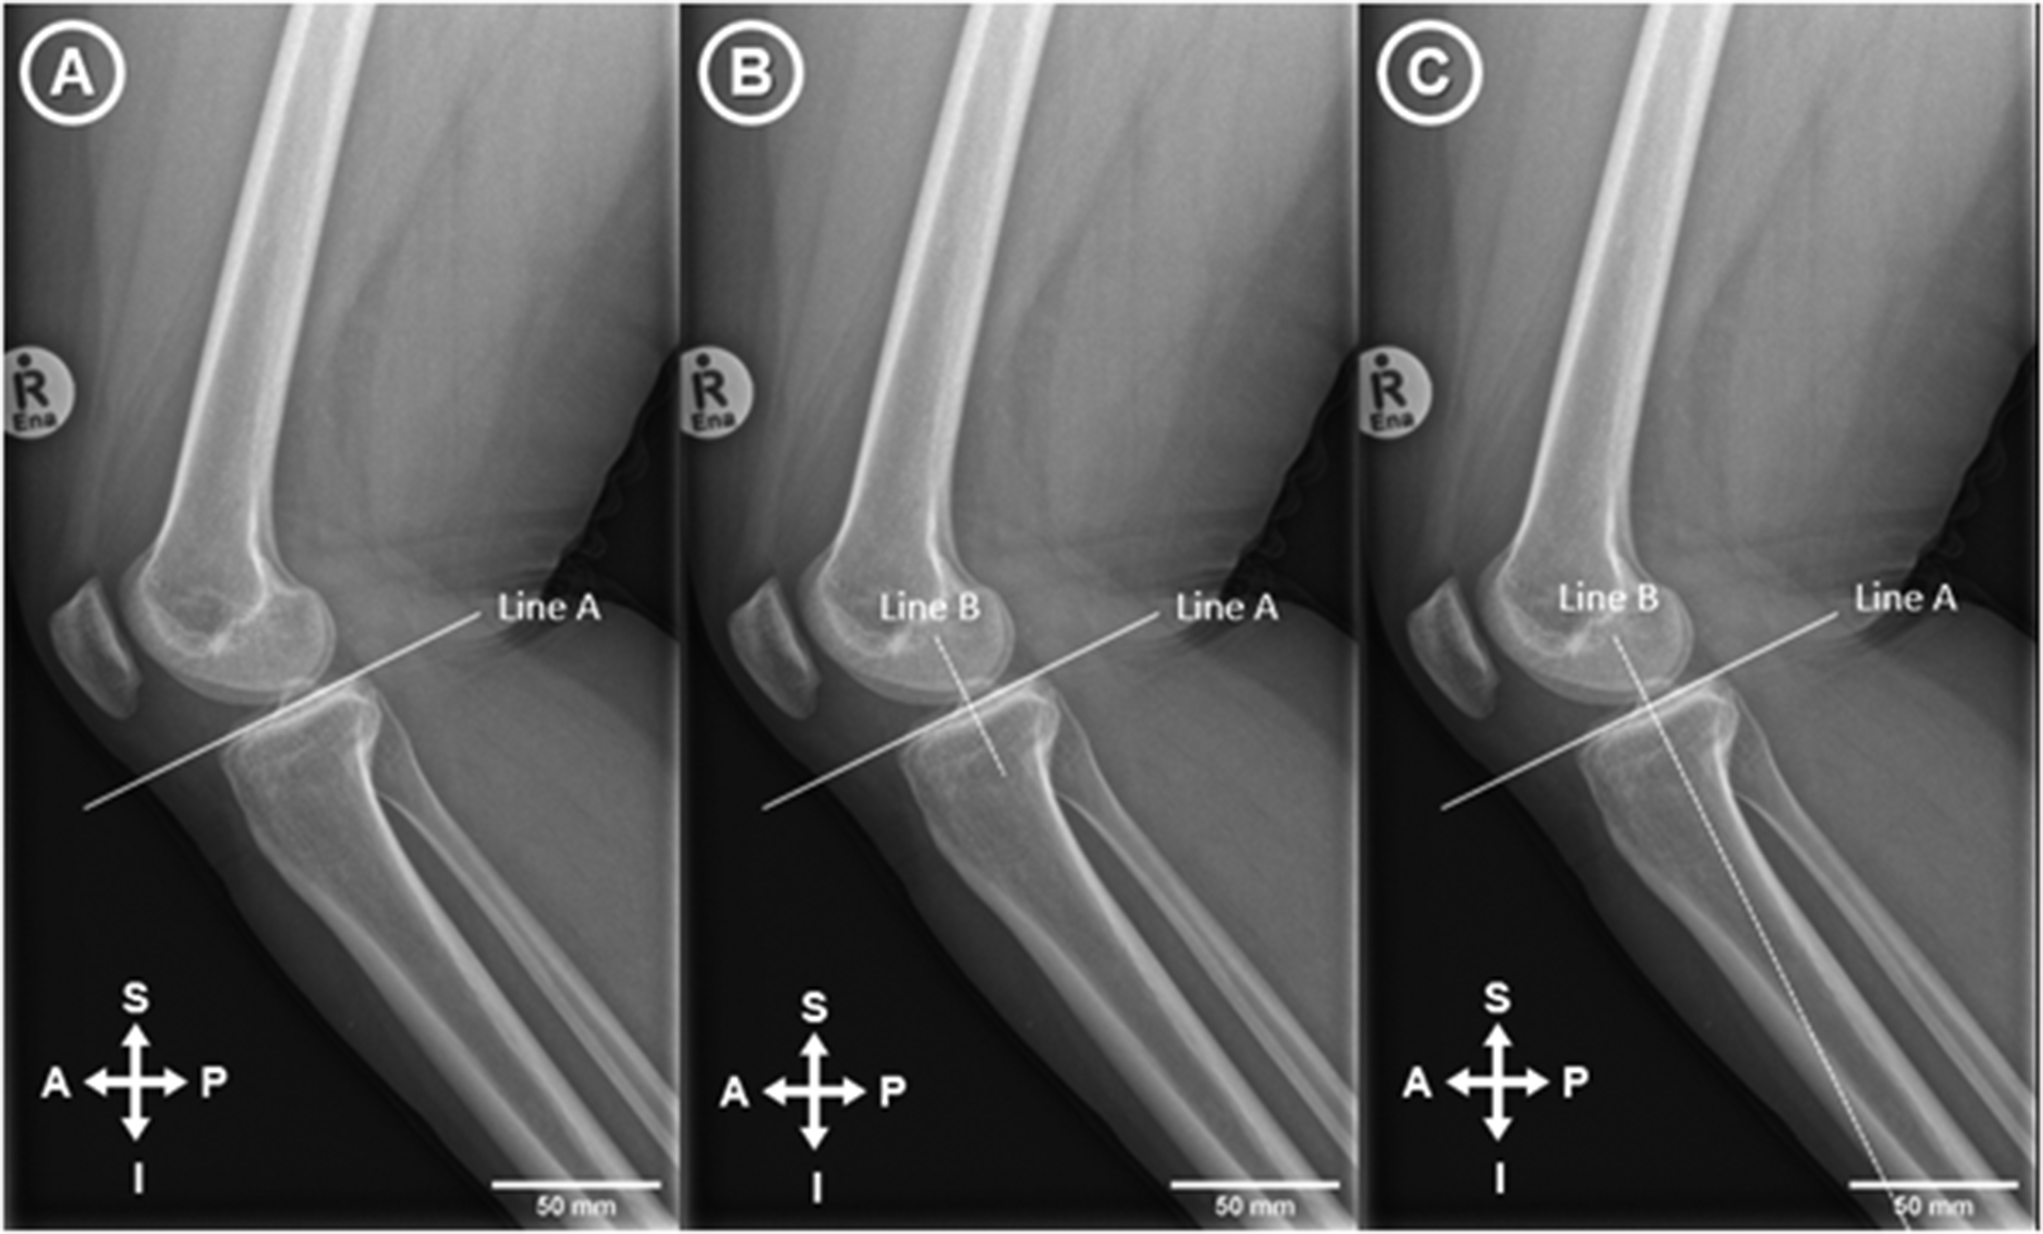

A morphometric study of posterior tibial slope differences by sex and ethnicity in a South African population

Posterior tibial slope (PTS) influences knee kinetics and kinematics. The purpose of this study was to investigate morphol...